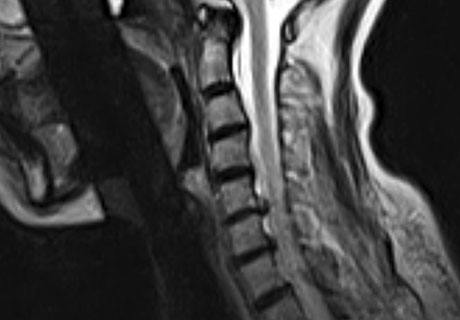

※ After 사진은 6개월 후 촬영된 모습으로, 파열된 디스크가 깨끗하게 흡수된 것을 확인할 수 있습니다.

모커리한방병원은 한양방협진 시스템으로 자체 보유한 MRI, X-ray 등의 영상의학적 기기를 통한 검진과 숙련된 한의사의 종합적인 진단을 통해 통증을 유발하는 정확한 원인 파악과 그에 맞는 치료가 가능합니다.